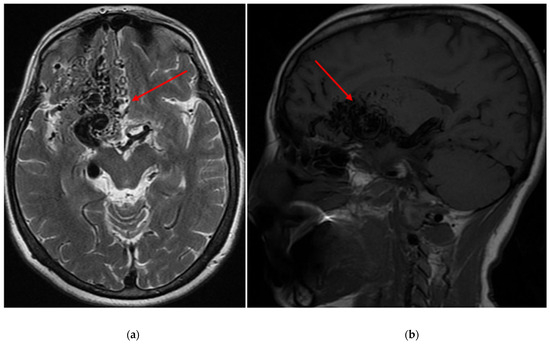

Demographic and clinical data of AVM sampling are shown in Table 1. Seventy patients presented with AVM-associated seizures, and 93 participants had no signs of seizures. Figure 1 and Figure 2 show magnetic resonance imaging (MRI) and cerebral angiography images of the brain of a patient with seizures associated with arteriovenous malformations. In total, 55.71% of subjects with seizures and 56.99% of AVMs without seizures were female. The age and BMI composition of cases and controls were comparable and not statistically significantly different (p > 0.05). Almost 95% of all participants underwent partial or total embolization (Table 2). The most common symptom was rupture, present in 41.98% of all participants.

Figure 1.

(a) An axial T2 magnetic resonance image of the brain depicts an arteriovenous malformation (AVM) situated within the right frontal lobe (red arrows), with a Spetzler-Martin grade of IV assigned to it (b) A sagittal T1 magnetic resonance image of the brain reveals the same AVM located within the right frontal lobe, also assigned a Spetzler-Martin grade of IV.